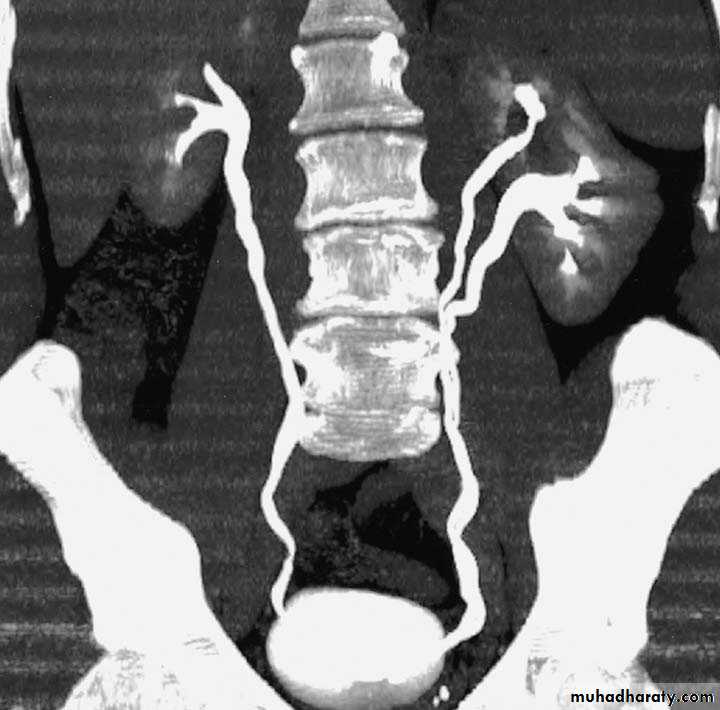

Postcaval (Retrocaval) ureter (Preureteral Vena Cava )

Urology

The right ureter pass behind the inferior vena cava

This might causes obstruction

Vascular abnormality

Incidence: about 1 in 1500

Although it is congenital, most patients present at 3rd or 4th decade.

Diagnosis: IVU

Treatment:

surgical correction involves ureteral division, with relocation and ureteroureteral or ureteropelvic reanastomosis,

usually with excision or bypass of the retrocaval segment, which can

be aperistaltic